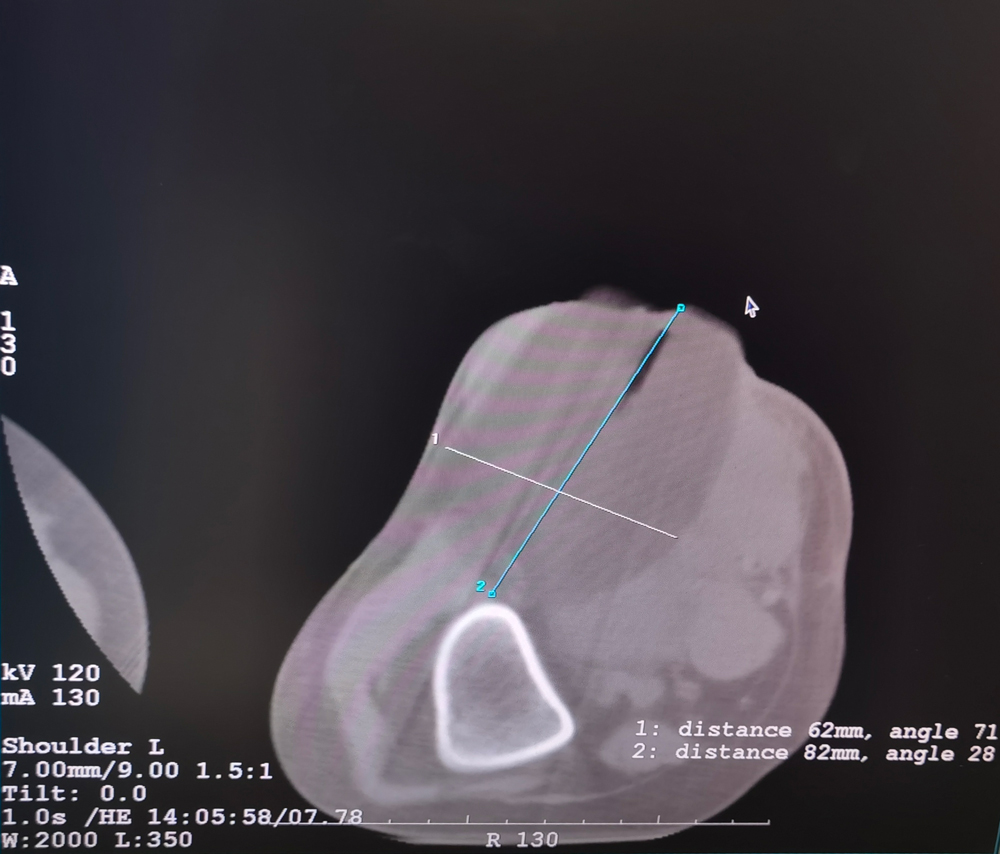

女,42歲,復(fù)發(fā)性脂肪瘤,病灶位于右側(cè)膝關(guān)節(jié),直徑大小13cm。采用雙針方案,共進(jìn)行6個(gè)凍融循環(huán),最大冰球直徑達(dá)8.2cm,術(shù)中多方位治療全面覆蓋病灶范圍。患者術(shù)后狀況良好。